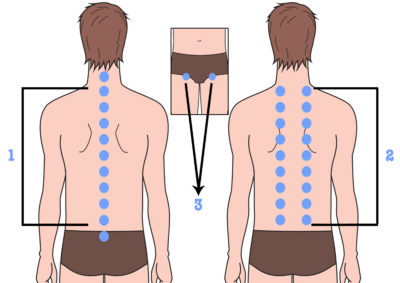

Berendezés kezelésére egy közös bizonyított hatású a különböző betegségek kezelésére az ízületek. kiküszöbölve fájdalom és gyulladás, elősegítik a szövetek regenerálódását és a méreg megszüntetése képződött ödéma. De, mint egy független terápiás szer az ilyen eszközöket nem használják, és része a komplex terápia formájában, amely az eszköz fizikoterápiás. Mivel az ilyen eszközök eltérnek a módszert az expozíció és ellenjavallatok. Felhasználás előtt győződjön meg róla, hogy konzultáljon orvosával.